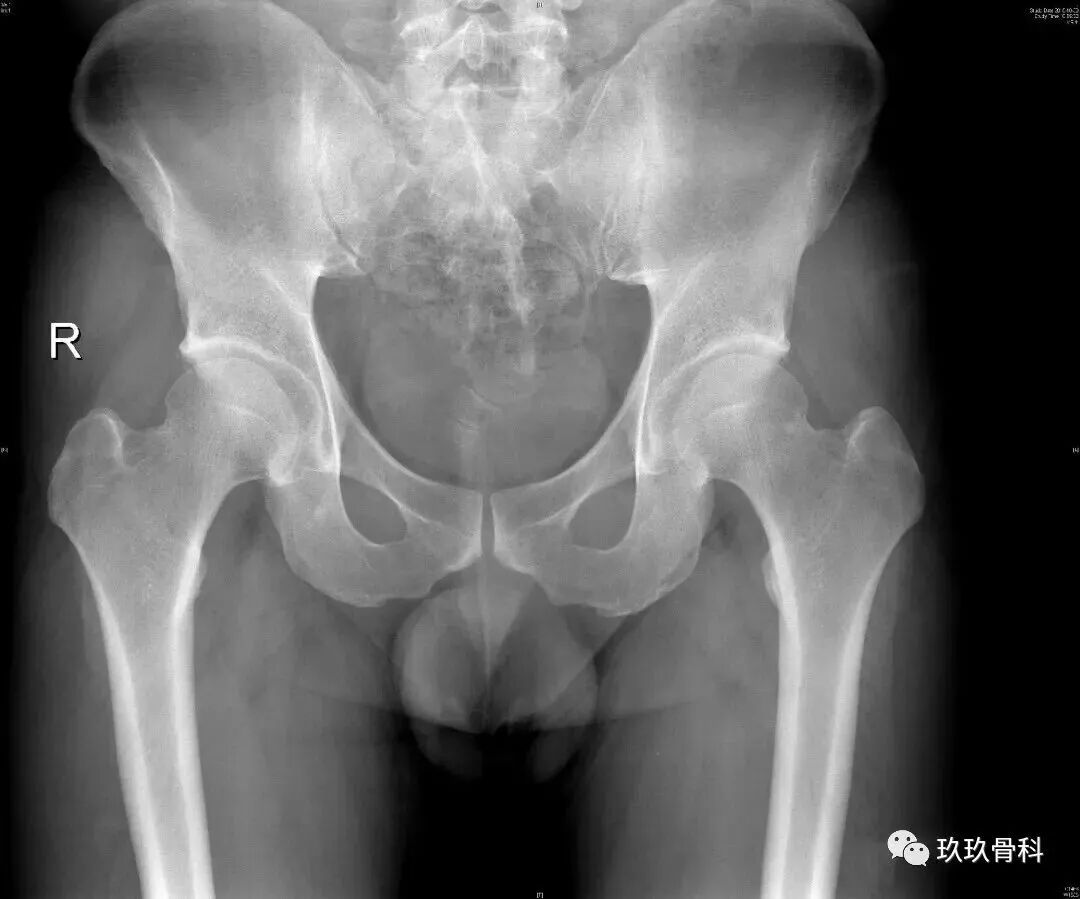

根据病情不同,术前检查有所不同,力求明确诊断。如果考虑髋关节撞击综合症,要做相应的特殊体位X片(骨盆正位+Dunn位),以及单髋盂唇核磁。不建议在当地医院检查,特殊体位检查需要有经验的医生和放射科医生合作才能完成,并且磁共振和CT这些检查档次也是不同的,在当地医院的检查只能作为参考。